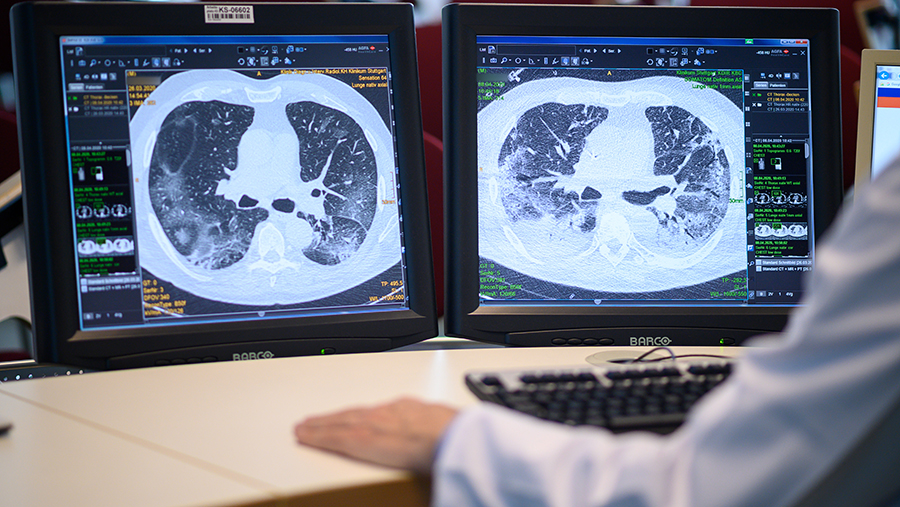

Фото: Global Look Press/dpa/Sebastian Gollnow

Приемная врача общей практики в английском Донкастере ошибочно разослала сотням пациентов сообщения о том, что у них якобы последняя стадия рака легких. Об этом 29 декабря сообщила газета The Times.

«Врач попросил заполнить (форму) DS1500 для вышеуказанного пациента. Диагноз — агрессивный рак легких с метастазами», — цитирует издание текст сообщения, который пациенты разместили в соцсетях.

DS1500 — это тип формы, которая позволяет неизлечимо больным людям претендовать на пособия.

Спустя 22 минуты пациенты получили сообщение с «искренними извинениями», где говорилось, что текст сообщения должен был звучать так: «Мы желаем вам очень счастливого Рождества и счастливого Нового года». Однако, по данным издания, это ситуацию не исправило: людей, которые на самом деле живут в ожидании своего диагноза, данный инцидент шокировал и довел до слез.